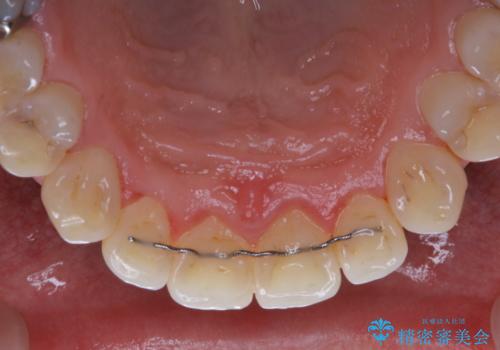

全体的にプラークや歯石が付着していて、歯肉炎が見られました。

状態に合った専門的な器具を使用して、歯質や歯肉へのダメージを抑えながらPMTC(自費クリーニング)60分コースを行いました。矯正治療後の保定装置がワイヤーの場合、フロス・糸ようじが通せないこと、歯ブラシがしずらいことなどにより、歯石プラークなどが付着しやすくなります。そのため専門的な器具による細かいケアを行うことがとても大切です。